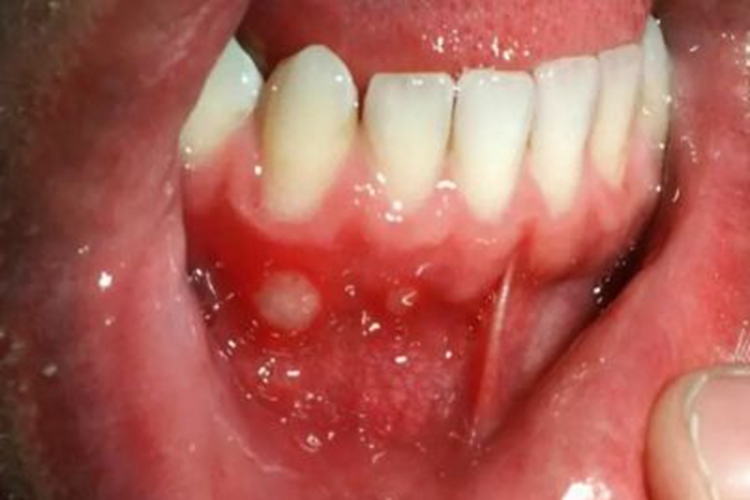

创伤性溃疡可在口腔黏膜出现水疱,之后破损后可形成溃疡或糜烂面,开始时可能仅有轻微疼痛或肿胀,溃疡为形态不整,有角的黏膜缺损,因唾液的浸渍,可使溃疡底发白,周边轻度炎性潮红,自觉疼痛。此外,表面渗出液和唾液混在一起,发生溃疡后可影响进食。

创伤性溃疡主要与口内持久的机械刺激有关,如残冠、残根、不良修复体、锐利的牙齿边缘等。